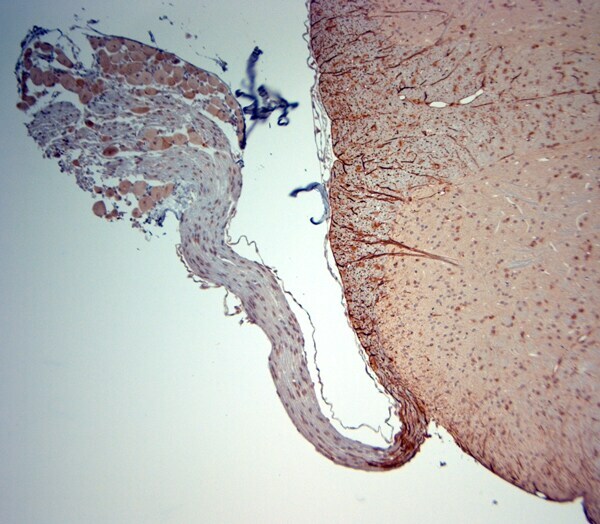

- Submitted by

- Invitrogen Antibodies (provider)

- Main image

- Experimental details

- IHC-P on paraffin sections of mouse spinal cord/DRG. The animal was perfused using Autoperfuser at a pressure of 130 mmHg with 300 mL 4% FA being processed for paraffin embedding. HIER: Tris-EDTA, pH 9 for 20 min using Thermo PT Module. Blocking: 0.2% LFDM in TBST filtered thru 0.2 µm. Detection was done using Novolink HRP polymer from Leica following manufacturers instructions; DAB chromogen: Candela DAB chromogen from Osenses. Primary antibody: dilution 1:1000, incubated 30 min at RT using Autostainer. Sections were counterstained with Harris Hematoxylin.